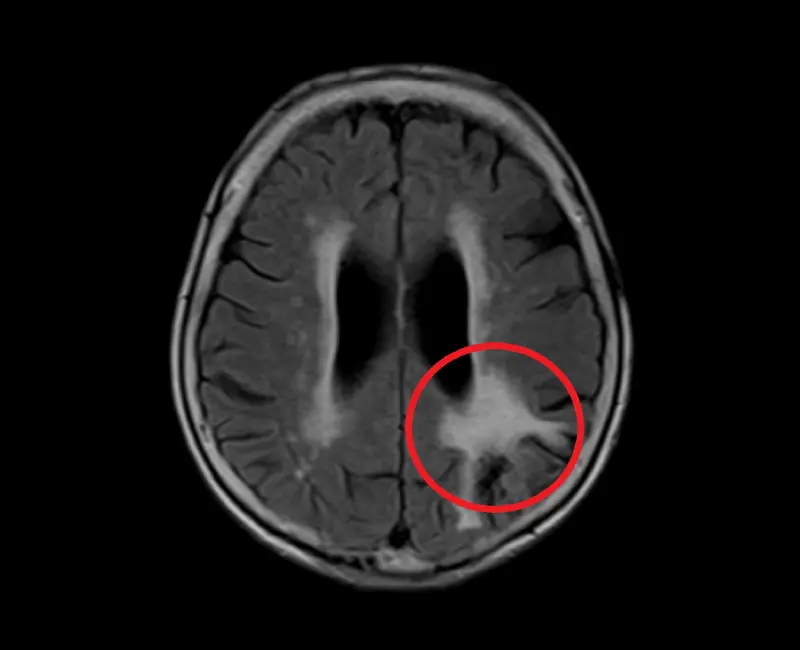

片頭痛(偏頭痛)

エストロゲン(女性ホルモン)との関わりが強く20代~40代の女性に起こりやすいと言われています。血管の拡張により血管周囲の神経が刺激され、ズキズキ拍動性の痛みが生じることが特徴です。吐き気を伴い、光をまぶしく感じたり、音にも敏感になったりします。また、頭痛の前兆として、目の前にキラキラした光が出現して視野がぼやける「閃輝暗点」という症状が現れる人もいます。30~40歳代の女性に限ると20%は片頭痛持ちと言われ、当クリニックでも最もご相談が多い頭痛の一つです。

20~40代の男性に多いことが特徴です。年に1~2回、片側の目の奥をえぐられるような痛みが1か月ほど毎日続きます。眼の後ろ側を通っている内頸動脈が拡張して炎症を引き起こすため、目の奥が痛むことが多いと言われています。